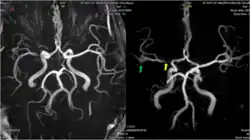

MRI and CT brain imaging is used to determine the severity of a stroke, and help guide treatment. Fluid attenuated inversion recovery (FLAIR) vascular hyperintensity (FVH) is a radiographic marker seen on brain imaging in acute ischaemic stroke. FVH can be used as a proxy for slow leptomeningeal collateral blood flow, and may help reveal which areas of brain tissue are potentially salvageable.[12]

A 2016 study compared patients awaiting carotid artery stenting for unilateral atherosclerotic plaques. Those with leptomeningeal collaterals evident on cranial angiography had a higher incidence of intracranial haemorrhage (ICH) after stenting. The authors argued that the presence of such collaterals on imaging should be considered a risk factor for ICH in patients where carotid stenting is otherwise indicated.[14]